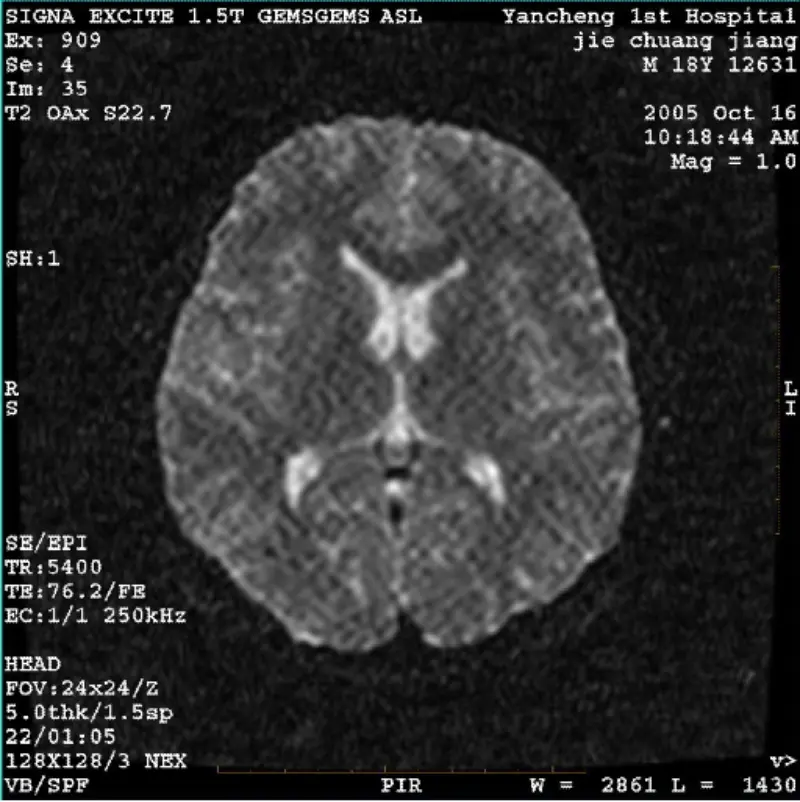

En savoir plusSYSTÈME : 1.5T Signa Twin Excite II (version logicielle 11.0M4) PROBLÈME/SYMPTO Image DWI (mode zoom et mode entier) et fiesta (mode zoom et mode entier) ayant Artefact visible en réticulation ou en velours côtelé, peu importe lors de l'utilisation de la bobine corporelle ou de la tête bobine......